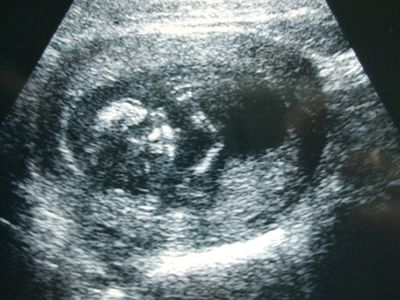

Ma voltunk dokinál. Volt Uh is. Bpd 26mm, 13 hétnek felel meg. Kicsit kisebb, mint a terhességi kor, de azt mondta a doki, hogy nem számít. Amúgy mindene megvan, jó a szívhangja és a placenta a hátsó falon tapad. Szóval minden ok. Remélem a mérete meg azért ekkora, mert pici lányka lesz :) De persze ezt még nem tudjuk.